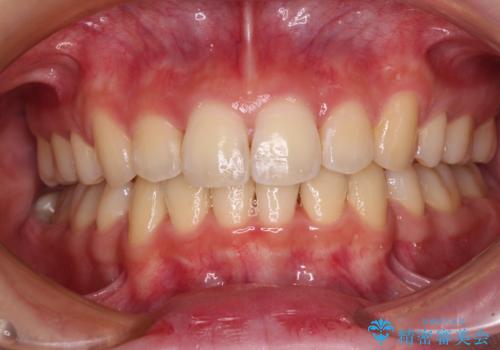

短期間で口元の突出感を改善 ワイヤー装置での抜歯矯正

上下左右4本抜歯する場合には、通常2年から2年半ほどの期間を要しますが、僅か1年半で終了することができました。